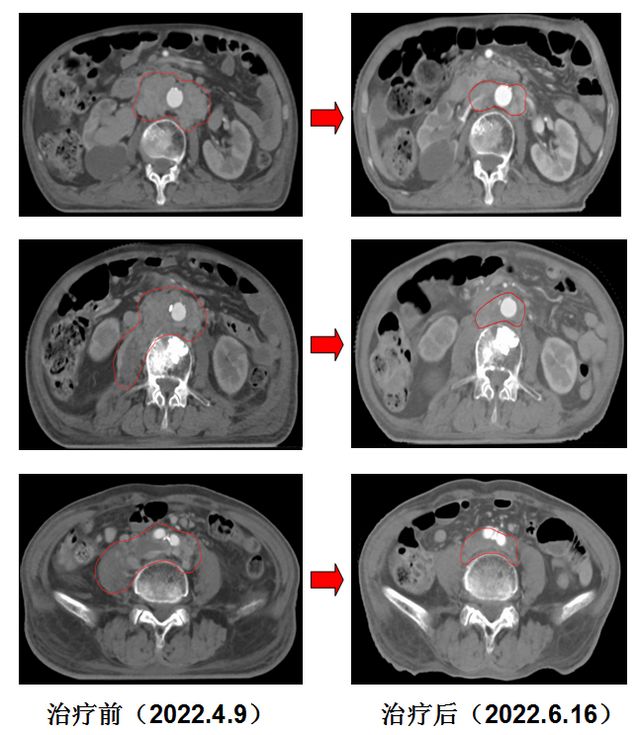

放疗后2个月,胡爷爷来院复查时已经可以行走了,双下肢的水肿完全消失,复查CT见腹膜后转移的淋巴结及右侧腰大肌转移病灶明显缩小,等待进一步治疗。